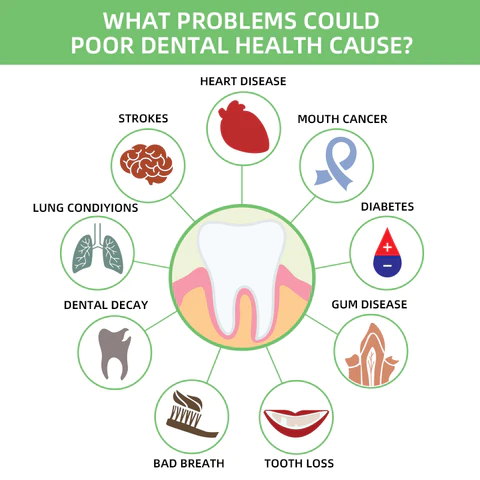

What Problems Could Poor Dental Health Cause?

- Oral diseases, while largely preventable, pose a major health burden for many countries and affect people throughout their lifetime, causing pain, discomfort, disfigurement, and even death.

- It is estimated that oral diseases affect nearly 3.5 billion people.

- Untreated dental caries (tooth decay) in permanent teeth is the most common health condition according to the Global Burden of Disease 2019.

- Treatment for oral health conditions is expensive and usually not part of universal health coverage (UHC).

- Most low- and middle-income countries do not have sufficient services available to prevent and treat oral health conditions.

- Oral diseases are caused by a range of modifiable risk factors common to many noncommunicable diseases (NCDs), including sugar consumption, tobacco use, alcohol use poor hygiene, and their underlying social and commercial determinants.